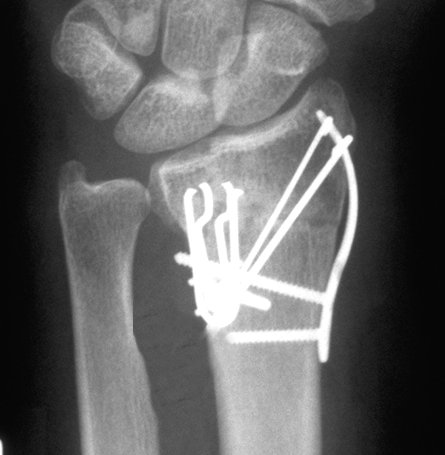

Case 2 Postop